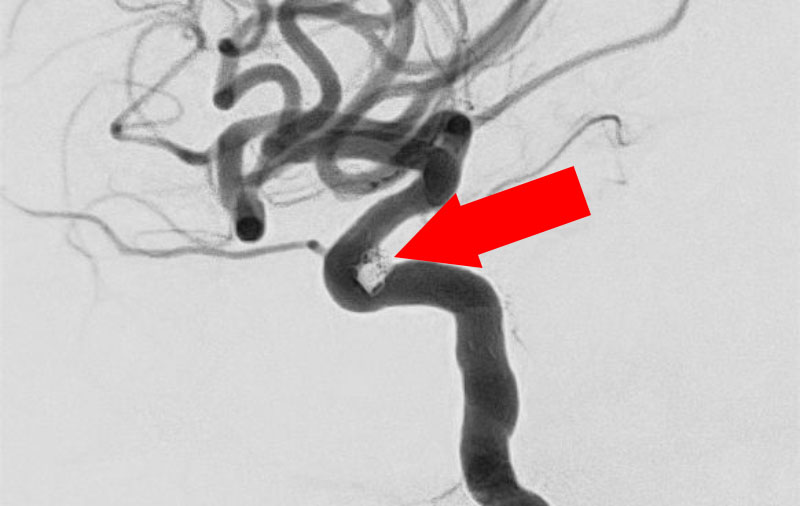

No.1631 手術前